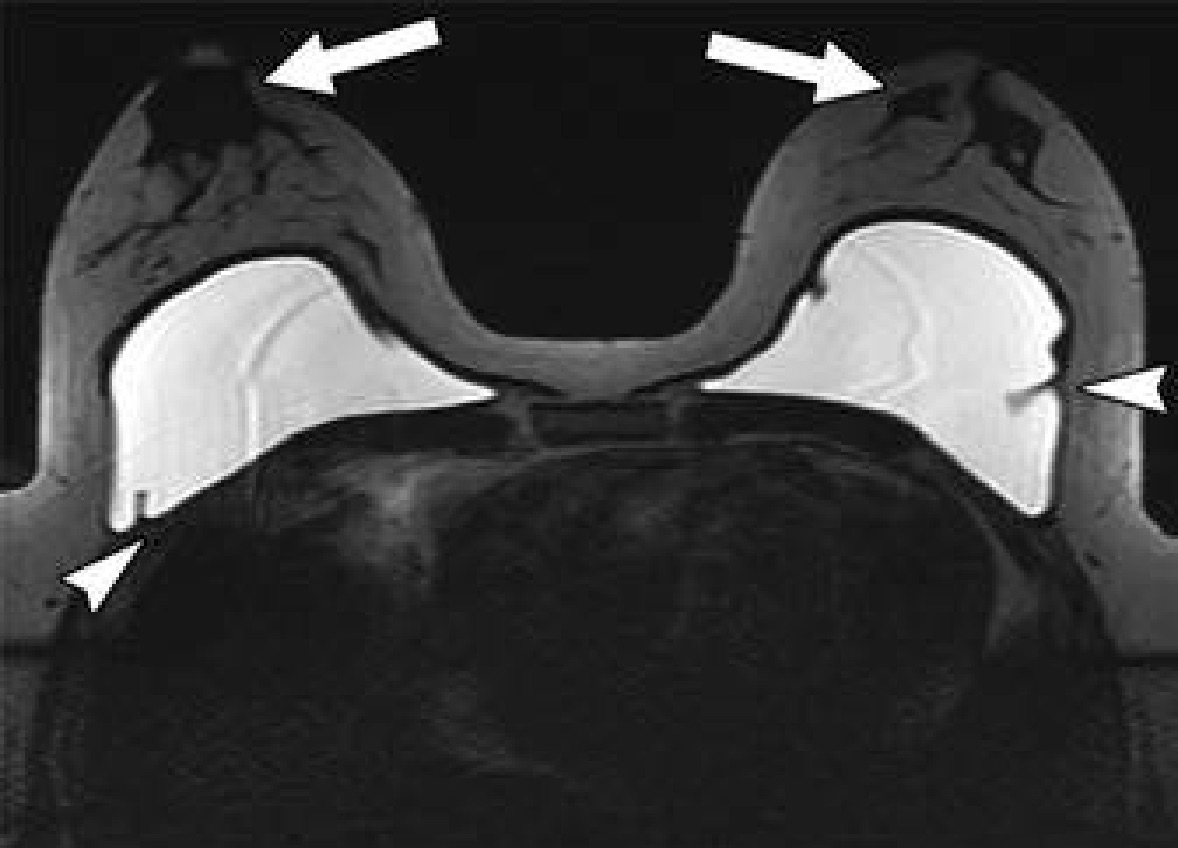

Related to gender affirmation surgery, silicone or saline breast implants in trans-females often evidence as incidental notations on chest radiography, computed tomography (CT) and MRI (Fig. 3), yet the most common body contouring gender affirmation surgery is subcutaneous mastectomy. Since the nipple-areola complex is preserved, retaining malignant transformation risk, Doo et al. recommend trans-males submit to regular postsurgical breast cancer screening. Likewise, trans-female patients who have undergone neoadjuvant hormone replacement therapy have an increased risk for breast cancer and should be routinely screened.

Fig. 3 — Single-shot fast spin-echo axial MR image of chest shows saline implants complicated by capsular contractions (arrowheads), with bilateral subareolar tissue (arrows) seen anterior to implants.